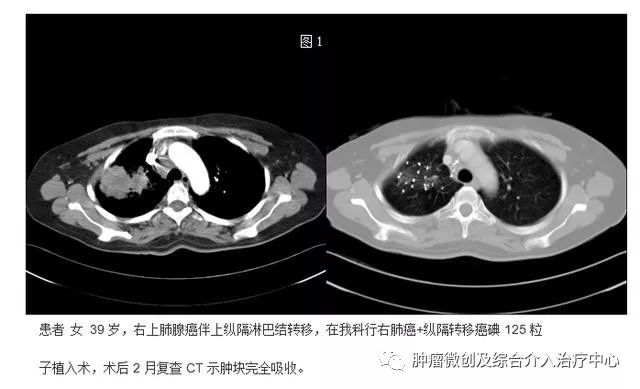

1.肺癌碘125粒子植入